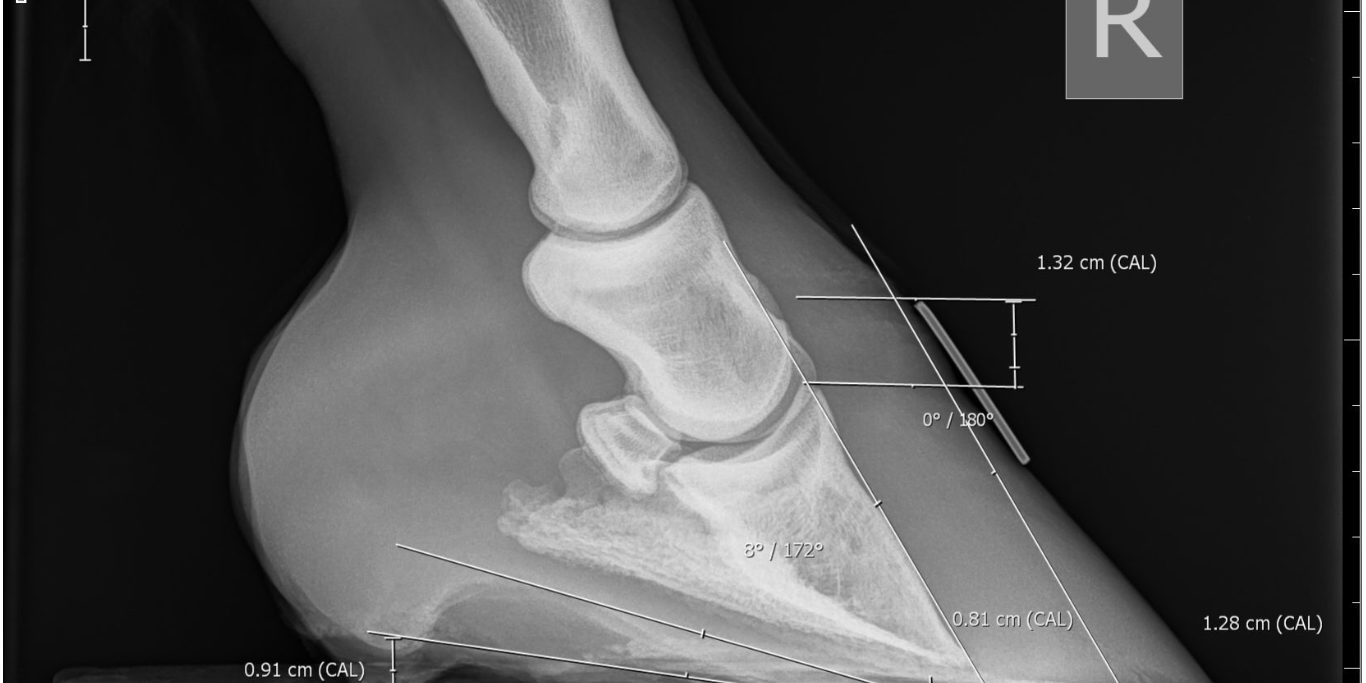

Changes to the internal hoof structures can be visible on x-rays and also on the outside of the hoof, such as with horizontal lines on the hoof wall. This can cause minor or severe issues depending on how much the coffin bone has rotated and/or descended.

Early intervention is key. The first and most important step is to call the vet and get them to come out if you suspect laminitis. They can then decide on the course of action. Your vet might suggest working with a good farrier or equine podiatrist to help make the horse more comfortable, as well as changes to diet and turnout (the focus of Part Two of this blog series). Further tests including X-rays may be taken after the acute phase, to check for rotation or distal descent.